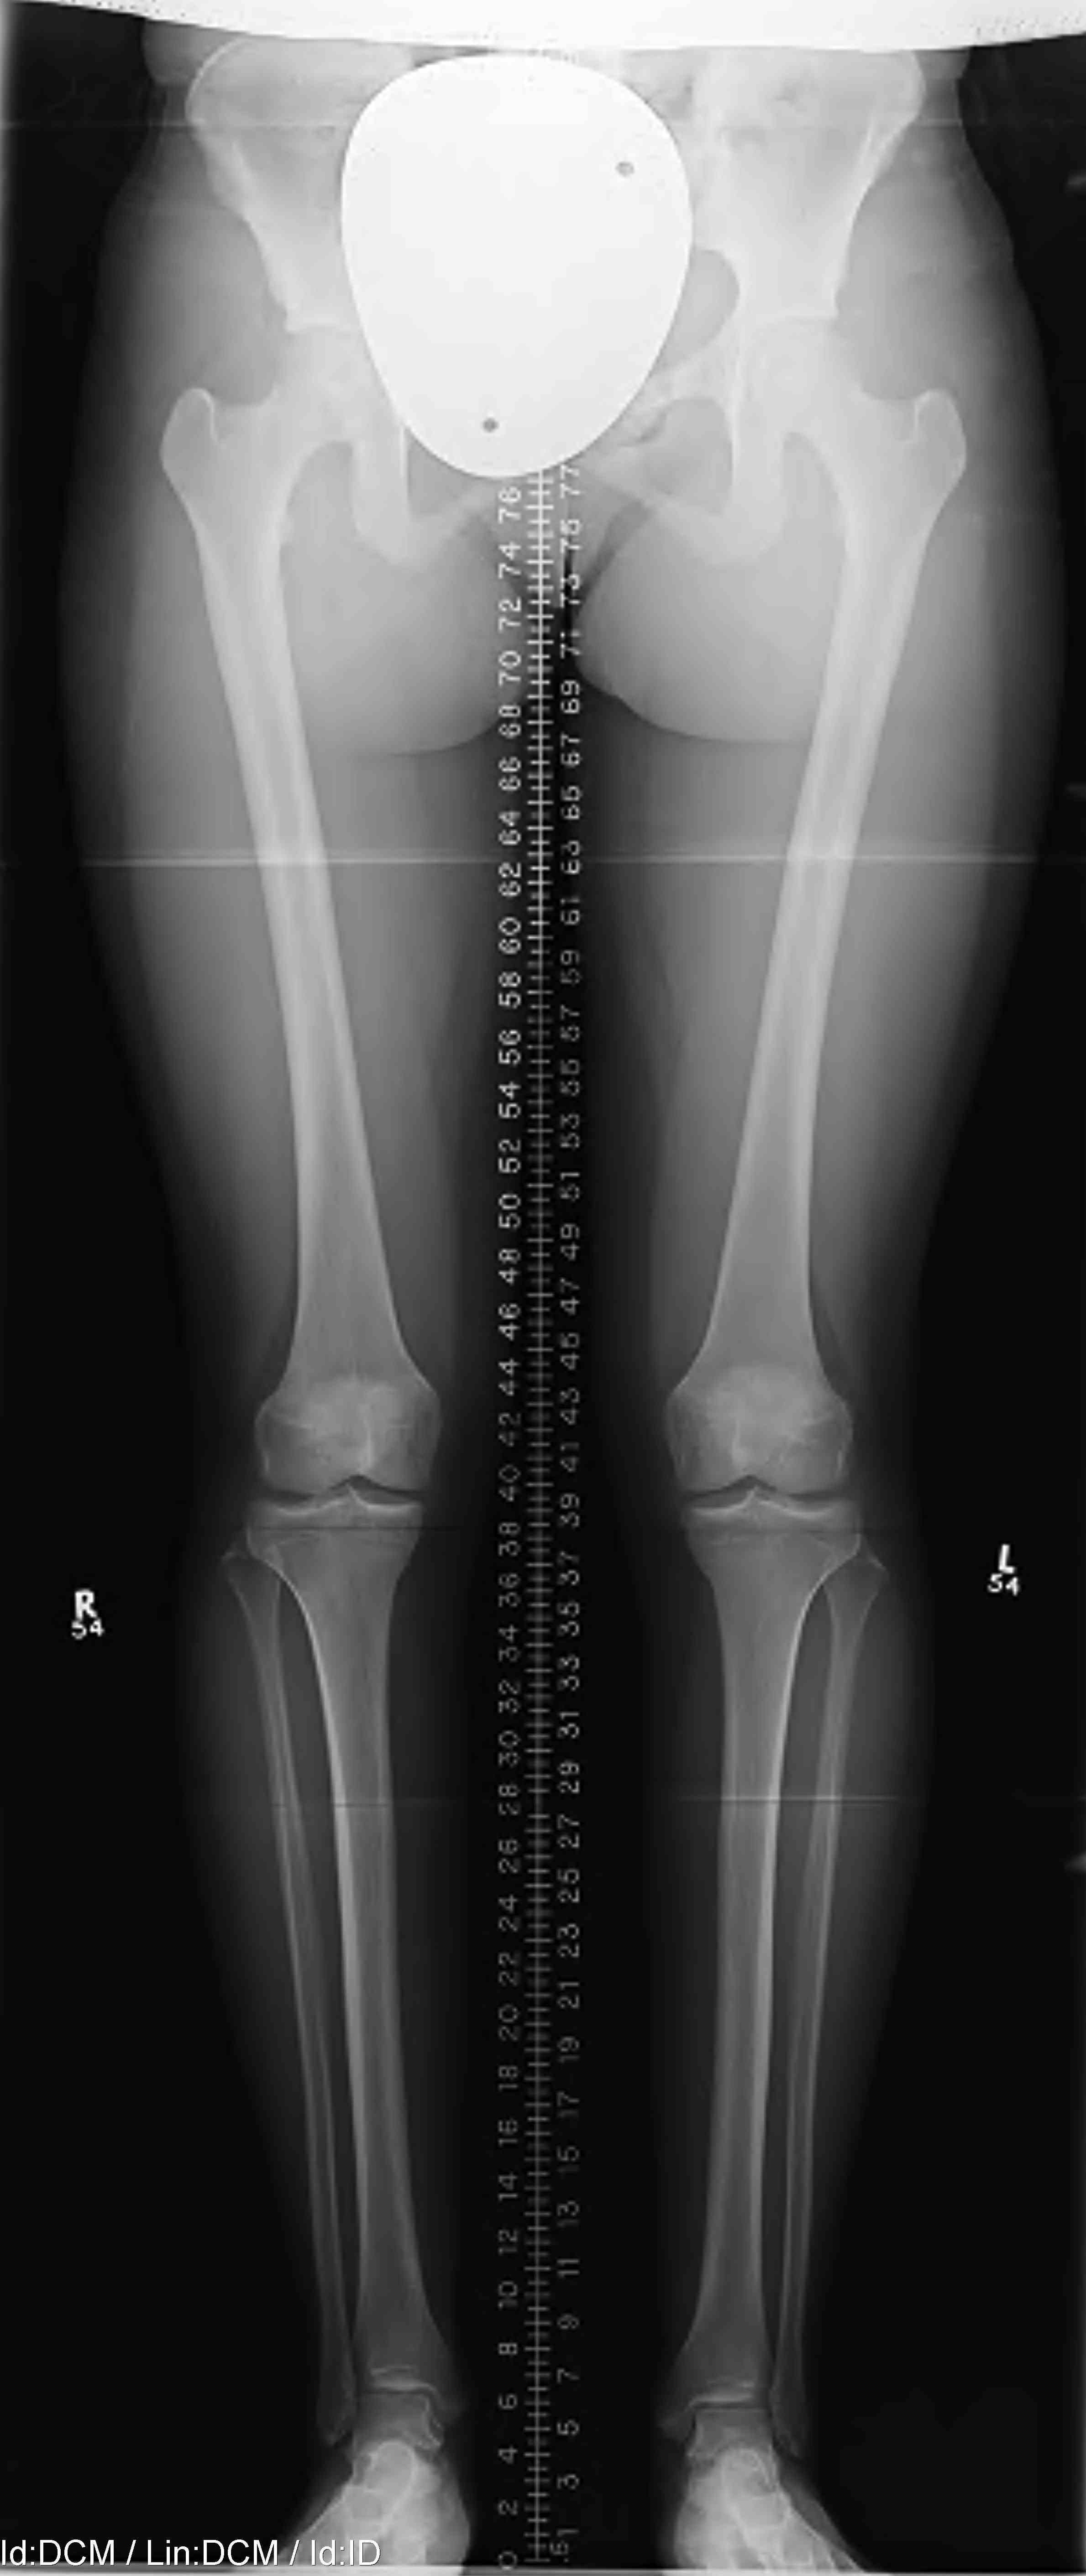

Long leg views

- assess for varus malalignment

Limb alignment

Mild varus of right knee

Mechanical axis passes medial to tip of medial tibial spine on long leg view

Varus malalignment left knee